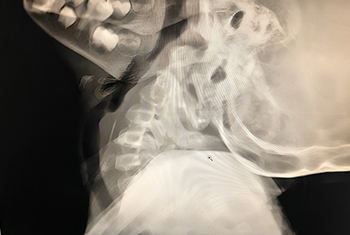

Comprehensive care for ear infections and hearing loss, including Tympanoplasty, Mastoidectomy, Ossiculoplasty and Stapedotomy/Stapedectomy for improved hearing outcomes.